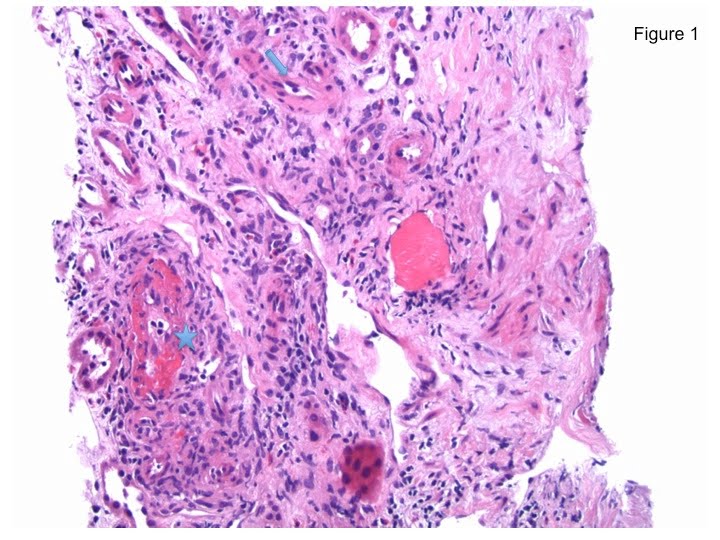

*Infiltrates seen inside the intima of the arteries (Figure 2, star) are lymphocytes and macrophages, which indicate Banff type 2 TCMR. See how the nuclei of those infiltrates look similar to the nuclei of the infiltrates in the interstitium (Figure 2, arrow) but they look different from the tubular epithelial nuclei that are perfectly rounded (Figure 2, circle).